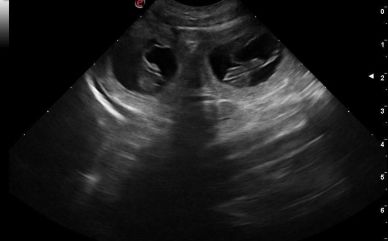

15.05.2024

Heute waren wir beim Ultraschall in der Tierarztpraxis meines Vertrauens. Und Juchuuu, es hat sich bestätigt, was ich schon vermutet habe. Wir erwarten mindestens 5 Welpen! Mangos extreme Anschmiegsamkeit, ihre Morgenübelkeit an machen Tagen und ihre ständige Müdigkeit waren schon sehr deutliche Anzeichen. Wir sind so happy und hoffen auf eine leichte Geburt!